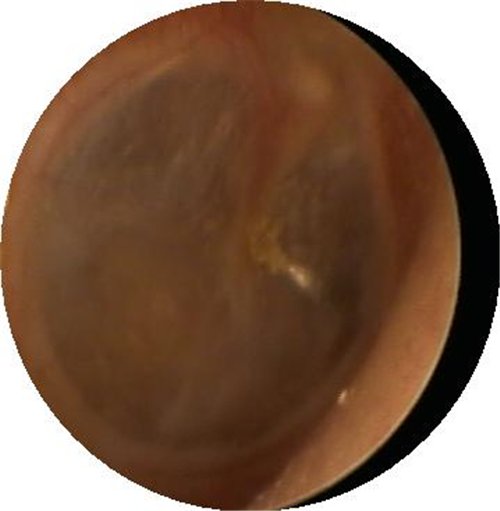

自愈的鼓膜穿孔